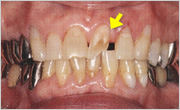

- ATTRITION

- 歯の咬耗(こうもう)

- 下顎前歯の咬耗

- かぶせ物の咬耗